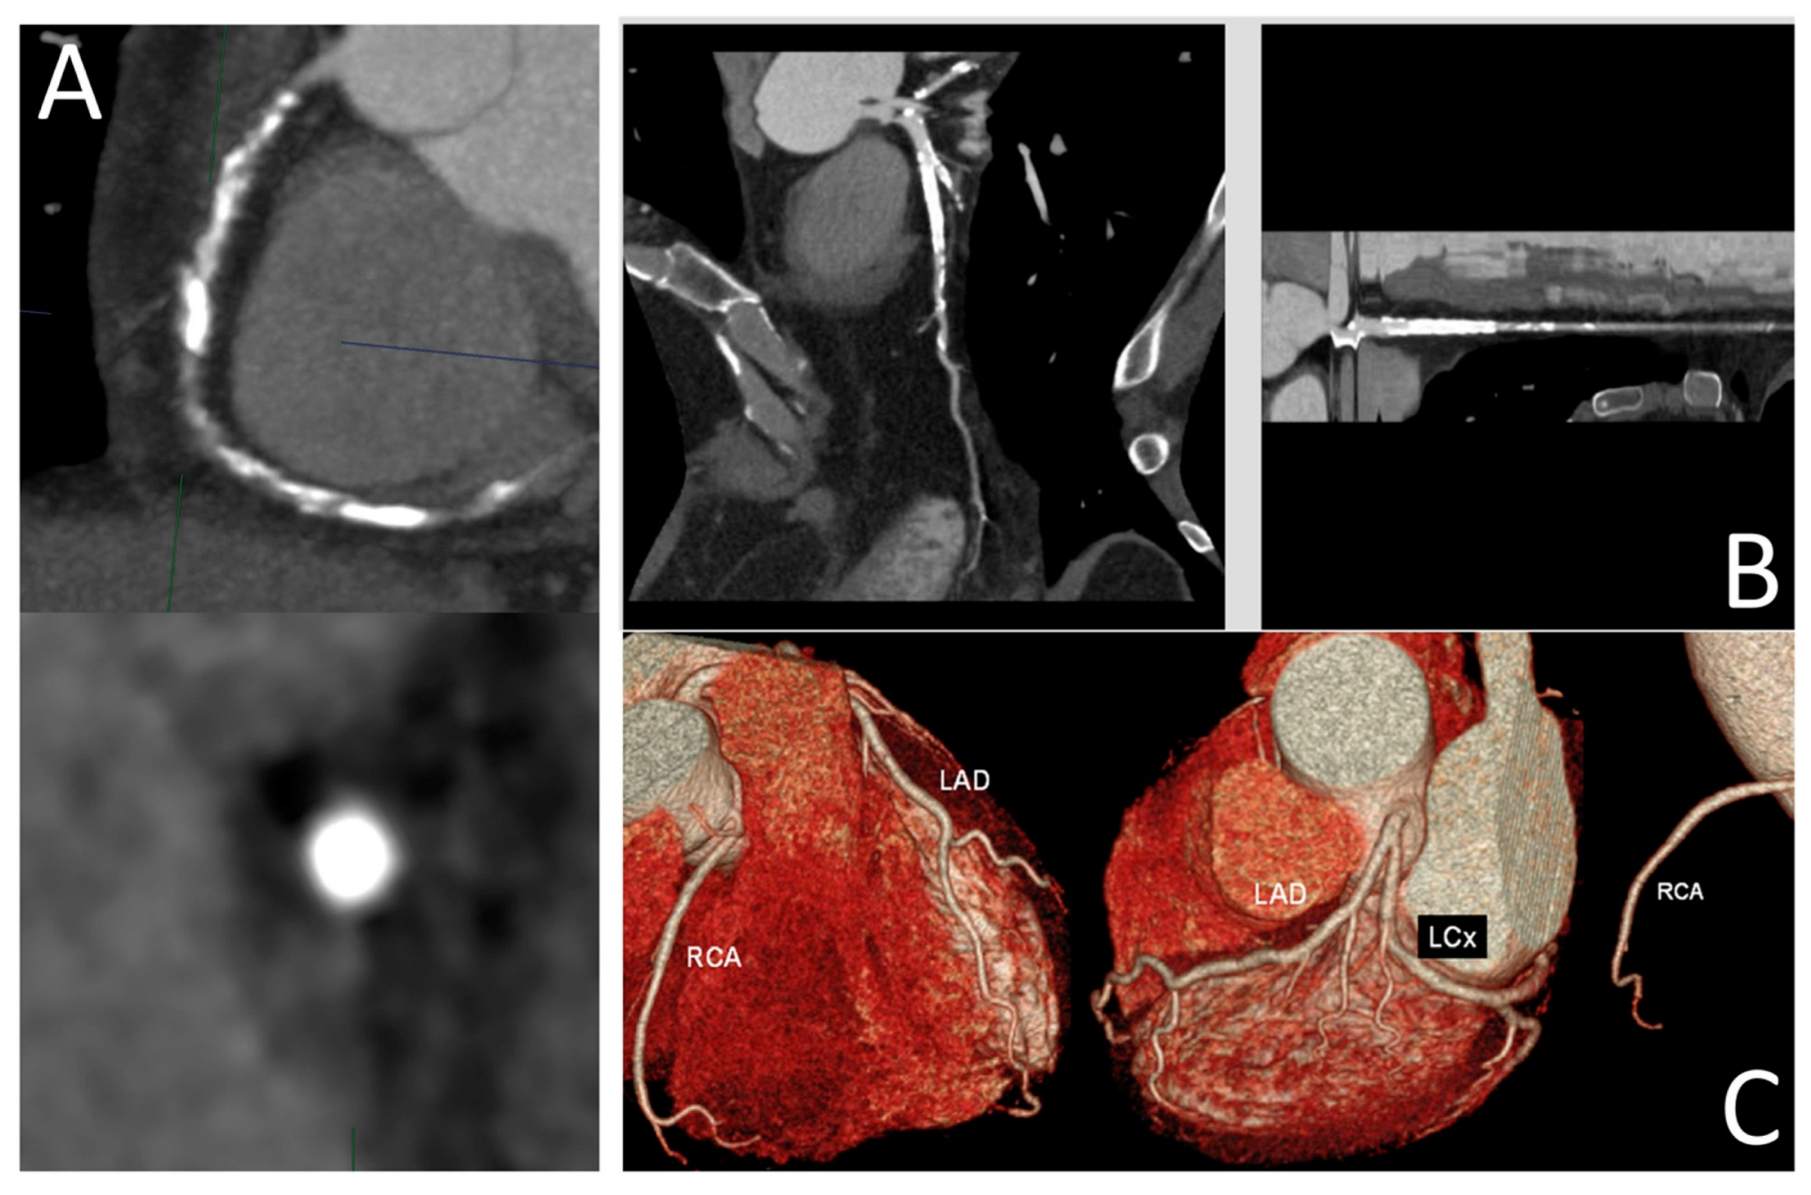

Panuccio et al. provide an overview of current coronary artery imaging modalities for diagnosis of chronic total occlusion (CTO), focusing on CTO-PCI. They discuss the strengths and limitations of each modality considered [7]. Optical coherence tomography (OCT), intravascular ultrasound (IVUS), and coronary CT angiography (CCTA) are reviewed in terms of their clinical value in assessment of CTO lesions. Despite the inherent superior spatial resolution (10–20 µm) allowing for detailed assessment of coronary wall and plaque morphology, OCT is limited by its penetration depth and invasive nature. In contrast, IVUS has several applications in CTO-PCI procedures, as it can be applied in proximal cap ambiguity, support in antegrade dissection and re-entry, support in reverse controlled antegrade and retrograde tracking, and integrated into stent deployment and optimization. IVUS-guided CTO-PCI is associated with higher procedural success rates, significantly lower procedural times, and a significantly lower risk of stent thrombosis. As a non-invasive imaging modality with the advantage of providing 3D visualizations, CCTA provides accurate assessment of plaque features and an overall vessel architecture (Figure 5). Furthermore, CCTA-based scores have shown better predictive performance than ICA-based scores. The authors of this article also discuss the future prospects of CTO interventions, including the use of AI/ML algorithms for automatic image segmentation and plaque quantification and the development of fusion imaging techniques consisting of combining CCTA with real-time fluoroscopy to provide real-time guidance during CTO-PCI procedures.

Figure 5. (A) Visualization of a high-calcified CTO plaque of a right coronary artery with the slab maximum intensity projection (MIP) technique; (B) curved and stretched multiplanar reconstruction of a left anterior descending CTO; (C) three-dimensional reconstruction of coronary arteries through the volume rendering approach. Reprinted with permission under open access from Panuccio et al. [7].